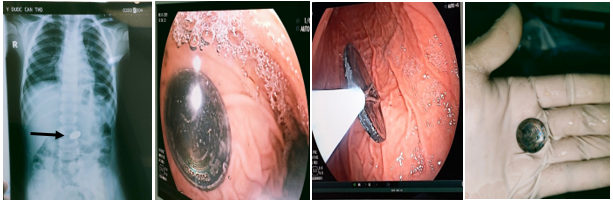

Ngày 9/11/2021, Bệnh viện Trường Đại học Y Dược Cần Thơ tiếp nhận bệnh nhi 44 tháng tuổi ở Long Mỹ, Hậu Giang trong tình trạng nuốt đồng xu ngày thứ 7. Trung tâm Nội soi – Nội soi can thiệp, Bệnh viện Trường vừa nội soi can thiệp thành công, gắp dị vật là đồng xu trong lòng dạ dày.

Sau khi nhập viện kiểm tra bằng chụp X-Quang, dị vật vẫn còn trong dạ dày. Trung tâm Nội soi – NSCT Bệnh viện Trường phối hợp với ê-kíp Gây mê thực hiện nội soi can thiệp để gắp dị vật. Sau 15 phút tiến hành, đồng xu đã được gắp ra ngoài, sau thủ thuật không biến chứng và bệnh nhi xuất viện trong ngày.